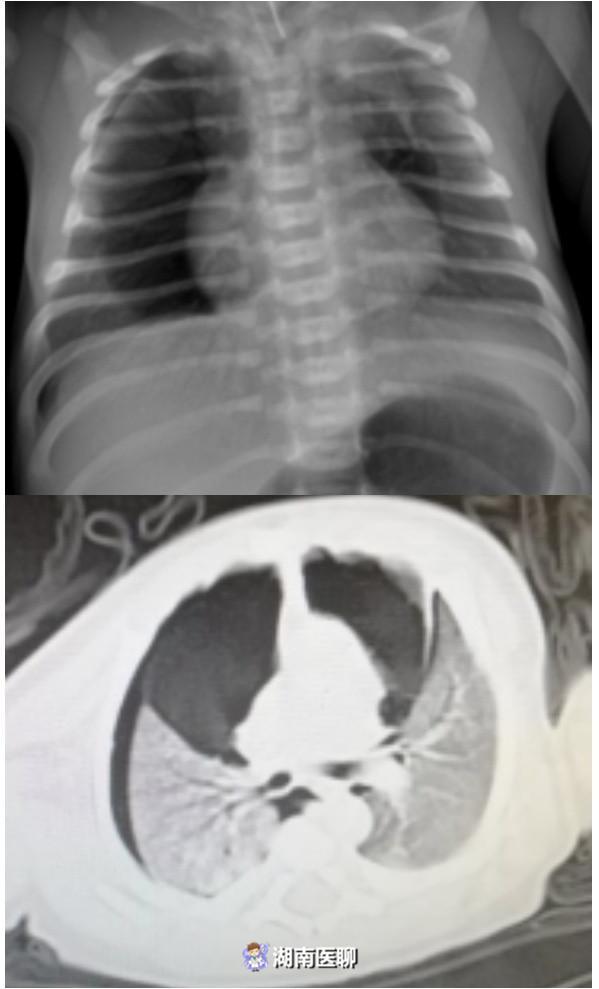

郴州一新生儿肺部破了个洞 一出生就呼吸困难

599x989 - 39KB - JPEG